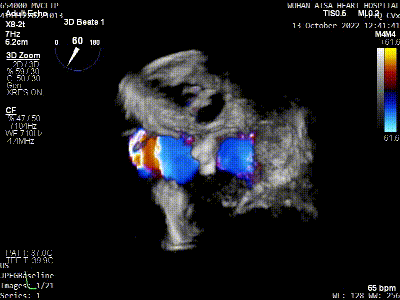

术前TEE评估

原发性二尖瓣反流(DMR),后叶P3区脱垂,反流程度4+,EROA 0.40cm2、RV 39ml;二尖瓣瓣口面积5.37cm²;二尖瓣前叶(A3)长度14.0mm,二尖瓣后叶长度(P3)长度12.2mm,脱垂宽度8.2mm,脱垂高度1.4mm;RA 2.9cm ,LA 3.6cm,左室射血分数LVEF56%,术前测量最大房间隔穿刺高度4.0cm

将MitraClip™XTR送入左房,由于左房太小,在达到骑跨过程中反复推进回撤CDS和稳定器,同时旋转SGC,达到骑跨的同时,保证Clip头端游离,且SGC在左房有深度。旋转M,同时顺时针往后旋转SGC借高度,使Clip垂直二尖瓣环平面,由于穿刺高度不够,Clip直接进入左室,这意味着操作要十分小心,左室组织复杂,稍有不慎将会造成组织损伤。使用A/P Konb中“A”旋钮借高度。确认垂直后,直接在左室打开Clip,3D外科视角,逆时针旋转使Clip夹臂处于11点-5点方向,回拉稳定器,使Clip处于3区脱垂区域,用“+/-”Knob中的“-”旋钮,使Clip更往后叶的同时增加操作高度,抓捕脱垂的瓣叶,关紧Clip后,反流从4+降低至0级,平均跨瓣压差2mmHg,左右肺静脉逆流均改善。前后叶活动度降低,后叶插入长度9mm,前叶插入12mm, 确认稳定性后释放Clip。释放后,即刻效果十分满意,手术圆满结束。